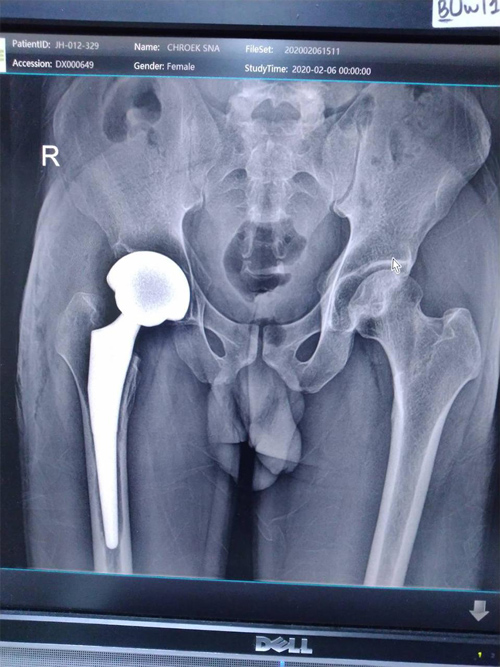

Dr. Weber and his partners participate in short term medical mission trips to Cambodia. Dr. Weber has had the pleasure of going twice now in 2018 and 2020. During these trips Dr. Weber performs total hip replacements on patients who normally would have no treatment options. To learn more and to see videos from the experience please click the links below.